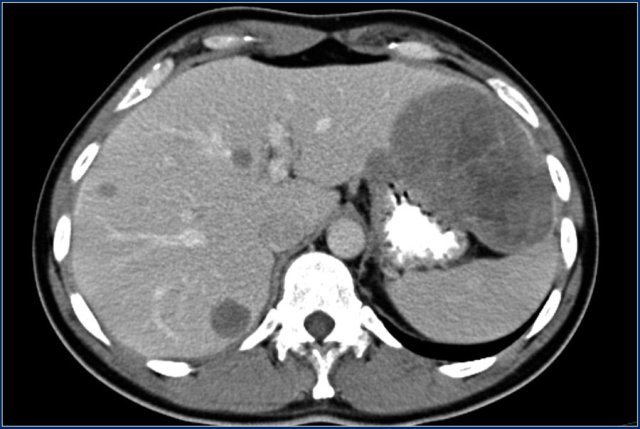

These images are of a patient who presented with peritoneal metastases.

The primary tumor proved to be a carcinoid of the appendix.

Liver metastases are usually hypervascular and can show central necrosis.

Same patient.

Four years after the initial CT multiple liver metastases are seen.

Notice hypervascular enhancement pattern in the late arterial phase.